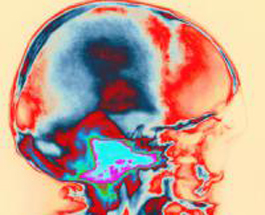

Сочетание транскраниальной магнитной стимуляции и электроэнцефалографии дало начало новому методу, позволяющему отследить сознательную деятельность мозга у травмированных пациентов.

Ученые из Миланского университета (Италия) и Университета Льежа (Бельгия) показали, что измерение уровня мозговых связей позволяет выявить у пациента, находящегося в вегетативном состоянии, сознание. Важно отметить, что эти измерения не зависят от целостности сенсорных или моторных путей, и от способности субъекта понимать и выполнять инструкции.

Как показали предыдущие исследования, этот подход позволяет различить состояния сознания — бодрствование и мечтание, а также сон или сон под анестезией.

Пациенты в вегетативном состоянии, которые бодрствовали (с открытыми глазами), но были без сознания, показали внутренние мозговые связи, напоминающие состояние под наркозом. Больные с минимальным уровнем сознания показали эффективную связь между различными областями мозга, независимо от способности общению.

Эти результаты подтверждают, что стимуляция мозга и ЭЭГ позволяет точно оценить сознательную активность пациентов с травмами мозга.